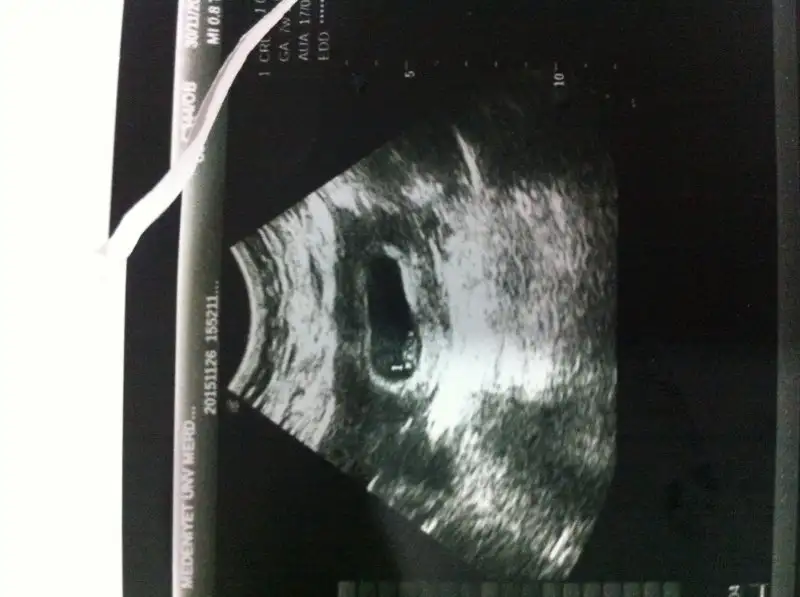

Kızlar benimde ultrasond kağıdıma bakarmısınız. Bebeğime karından bakıldı bugun çekildi. 7hafta 1 günlük hamileyim